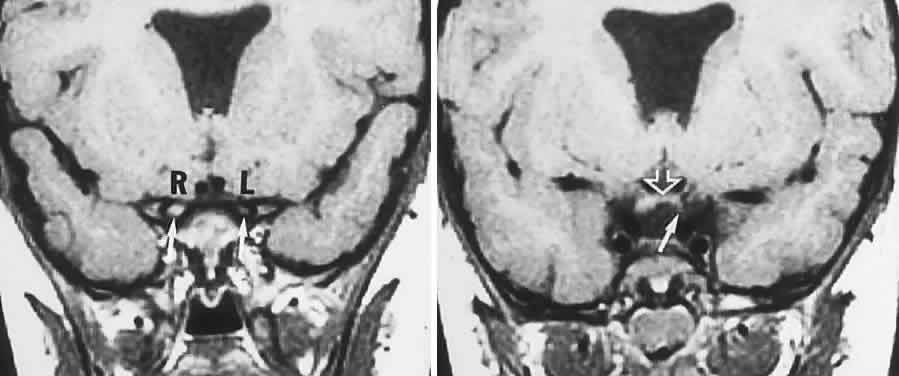

CONGENITAL HAMARTOMA SYNDROMES

The “neurophakomatoses” are a diverse group of disorders nosologically related by the presence of hamartomatous lesions, and, indeed, the term “hereditary hamartomatosis” is a more accurate description. However, whereas neurofibromatosis, tuberous sclerosis, and von Hippel-Lindau disease are transmitted with irregular dominance and considerable variation in penetrance, no hereditary basis of Sturge-Weber or angio-osteohypertrophy (Klippel-Trenaunay-Weber) syndrome has been established.

A hamartoma is a tumor of anomalous origin composed of elements normally present in the tissue in which it originates and with a limited capacity for proliferation. The following tumors may be classified as hamartomas: (1) in neurofibromatosis: optic gliomas (see Chapter 6), neurofibromas, and ganglioneuromas; (2) in tuberous sclerosis: retinal and cerebral astrocytomas, cutaneous angiofibromas (“adenoma sebaceum”), rhabdomyomas, and leiomyomas; (3) in von Hippel-Lindau disease: hemangioblastomas of the cerebellum and retina (including optic nerve head) and renal hypernephromas or cysts; (4) in Sturge-Weber disease: facial and choroidal cavernous hemangiomas and meningeal angiomatous malformations; and (5) in Klippel-Trenaunay-Weber syndrome: cutaneous nevi, visceral and limb hemangiomas, and orbitofacial venous varices.

If all disorders with neurocutaneous manifestations are considered, the term phakomatoses (Greek, phakos, “spot,” “birthmark”) is appropriate, and the catalog of “related” disorders becomes cumbersome. “The Phakomatoses,” Volume 14 of Vinken and Bruyn's Handbook of Clinical Neurology, is extraordinarily complete and serves as a source of detailed clinical descriptions of these diseases.146 Syndromes characterized by vascular hamartomas, that is, retinal-cerebellar angiomatosis (von Hippel-Lindau), and other angiomatous malformations, are discussed in Volume 2, Chapter 17.